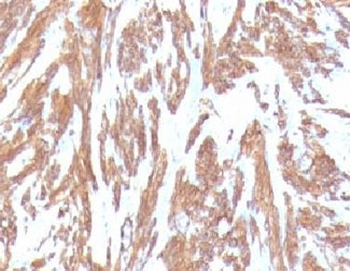

IHC: Formalin-fixed, paraffin-embedded Leiomyosarcoma stained with Smooth Muscle Actin antibody (clone SPM332).